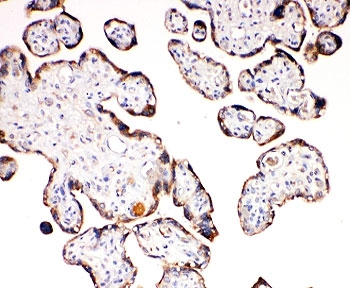

Aquaporin 6 is a protein in humans that is encoded by the AQP6 gene. The aquaporins (AQPs) are a family of water-transporting proteins that facilitate osmotically driven water movement across cell plasma membranes. Unlike other aquaporins, AQP6 functions not as a water channel but as an anion-selective channel. Single-channel analyses have shown AQP6 to flicker rapidly between closed and open status.

An amino acid sequence from the C-terminus of human Aquaporin 6 (EPLKKESQPGSGAVEMESV) was used as the immunogen for this Aquaporin 6 antibody.